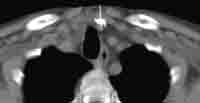

Abb. 1.2. a-c: CT- gesteuerte PEIT eines Nebenschilddrüsenadenom-Rezidives. Unmittelbar nach der PEIT kam es zu einer sofortigen Normalisierung des Parathormonspiegels als Ausdruck eines Therapie-Response.

![]() |

| Abb. 1.2. a | Abb. 1.2. b | Abb. 1.2. c |